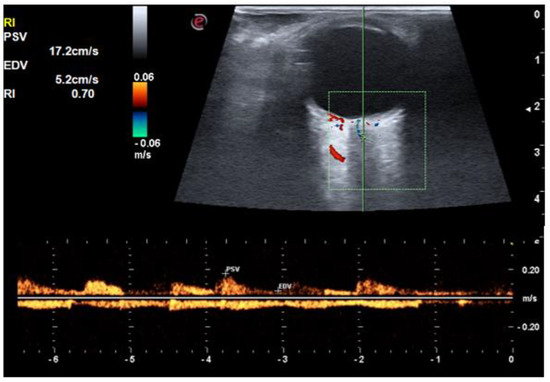

| PSV of central retinal artery (cm/s) | 16.1 ± 1.9 | 15.8 ± 3.1 | 14.2 ± 2.7 | 0.010 |

| EDV of central retinal artery (cm/s) | 5.1 ± 0.7 | 4.8 ± 1.1 | 3.9 ± 1.0 | <0.001 |

| RI of central retinal artery | 0.68 ± 0.03 | 0.69 ± 0.03 | 0.72 ± 0.04 | <0.001 |